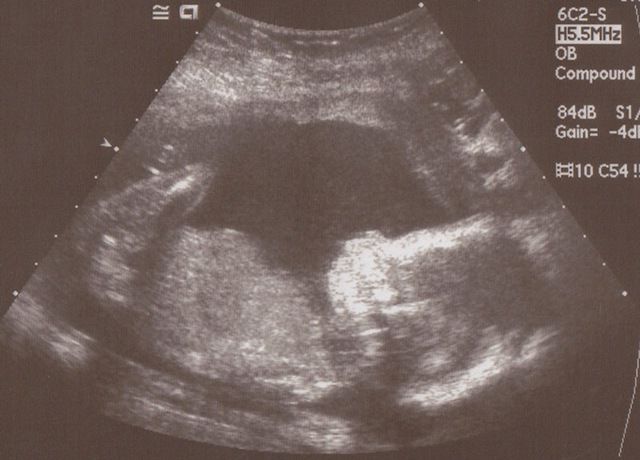

face

A face!  It’s sideways, with the top being to the right.  You can also kind of see a hand above the face, like the baby’s waving.